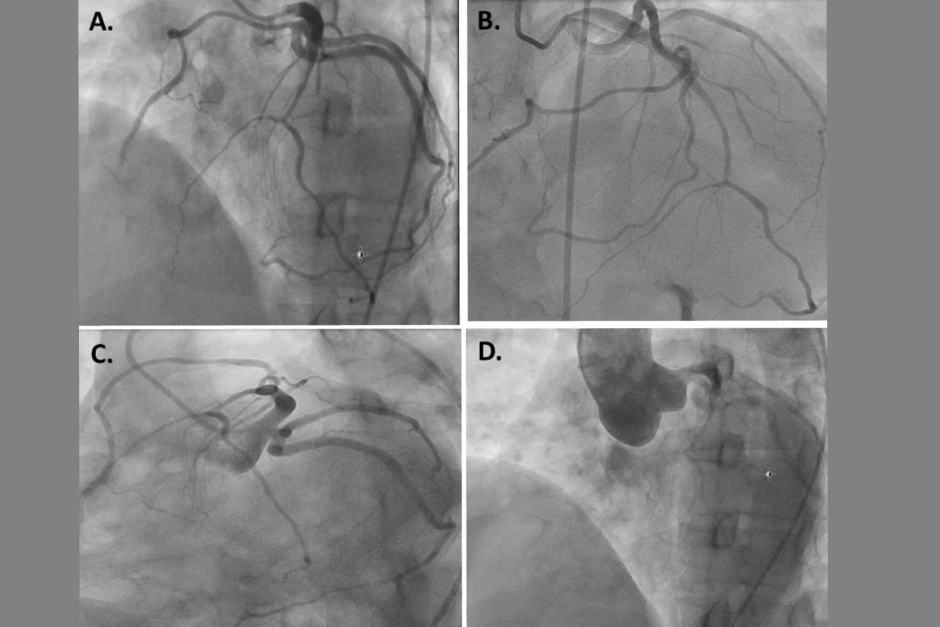

A coronary angiogram is a specialized imaging test used to check for blockages or narrowing in the coronary arteries. It involves injecting a contrast dye into the blood vessels and using X-ray imaging to visualize blood flow to the heart. This test is a critical tool for identifying heart conditions and determining the need for treatments such as angioplasty or bypass surgery.

- X-ray Imaging: A series of X-rays are taken to observe the blood flow and identify blockages.